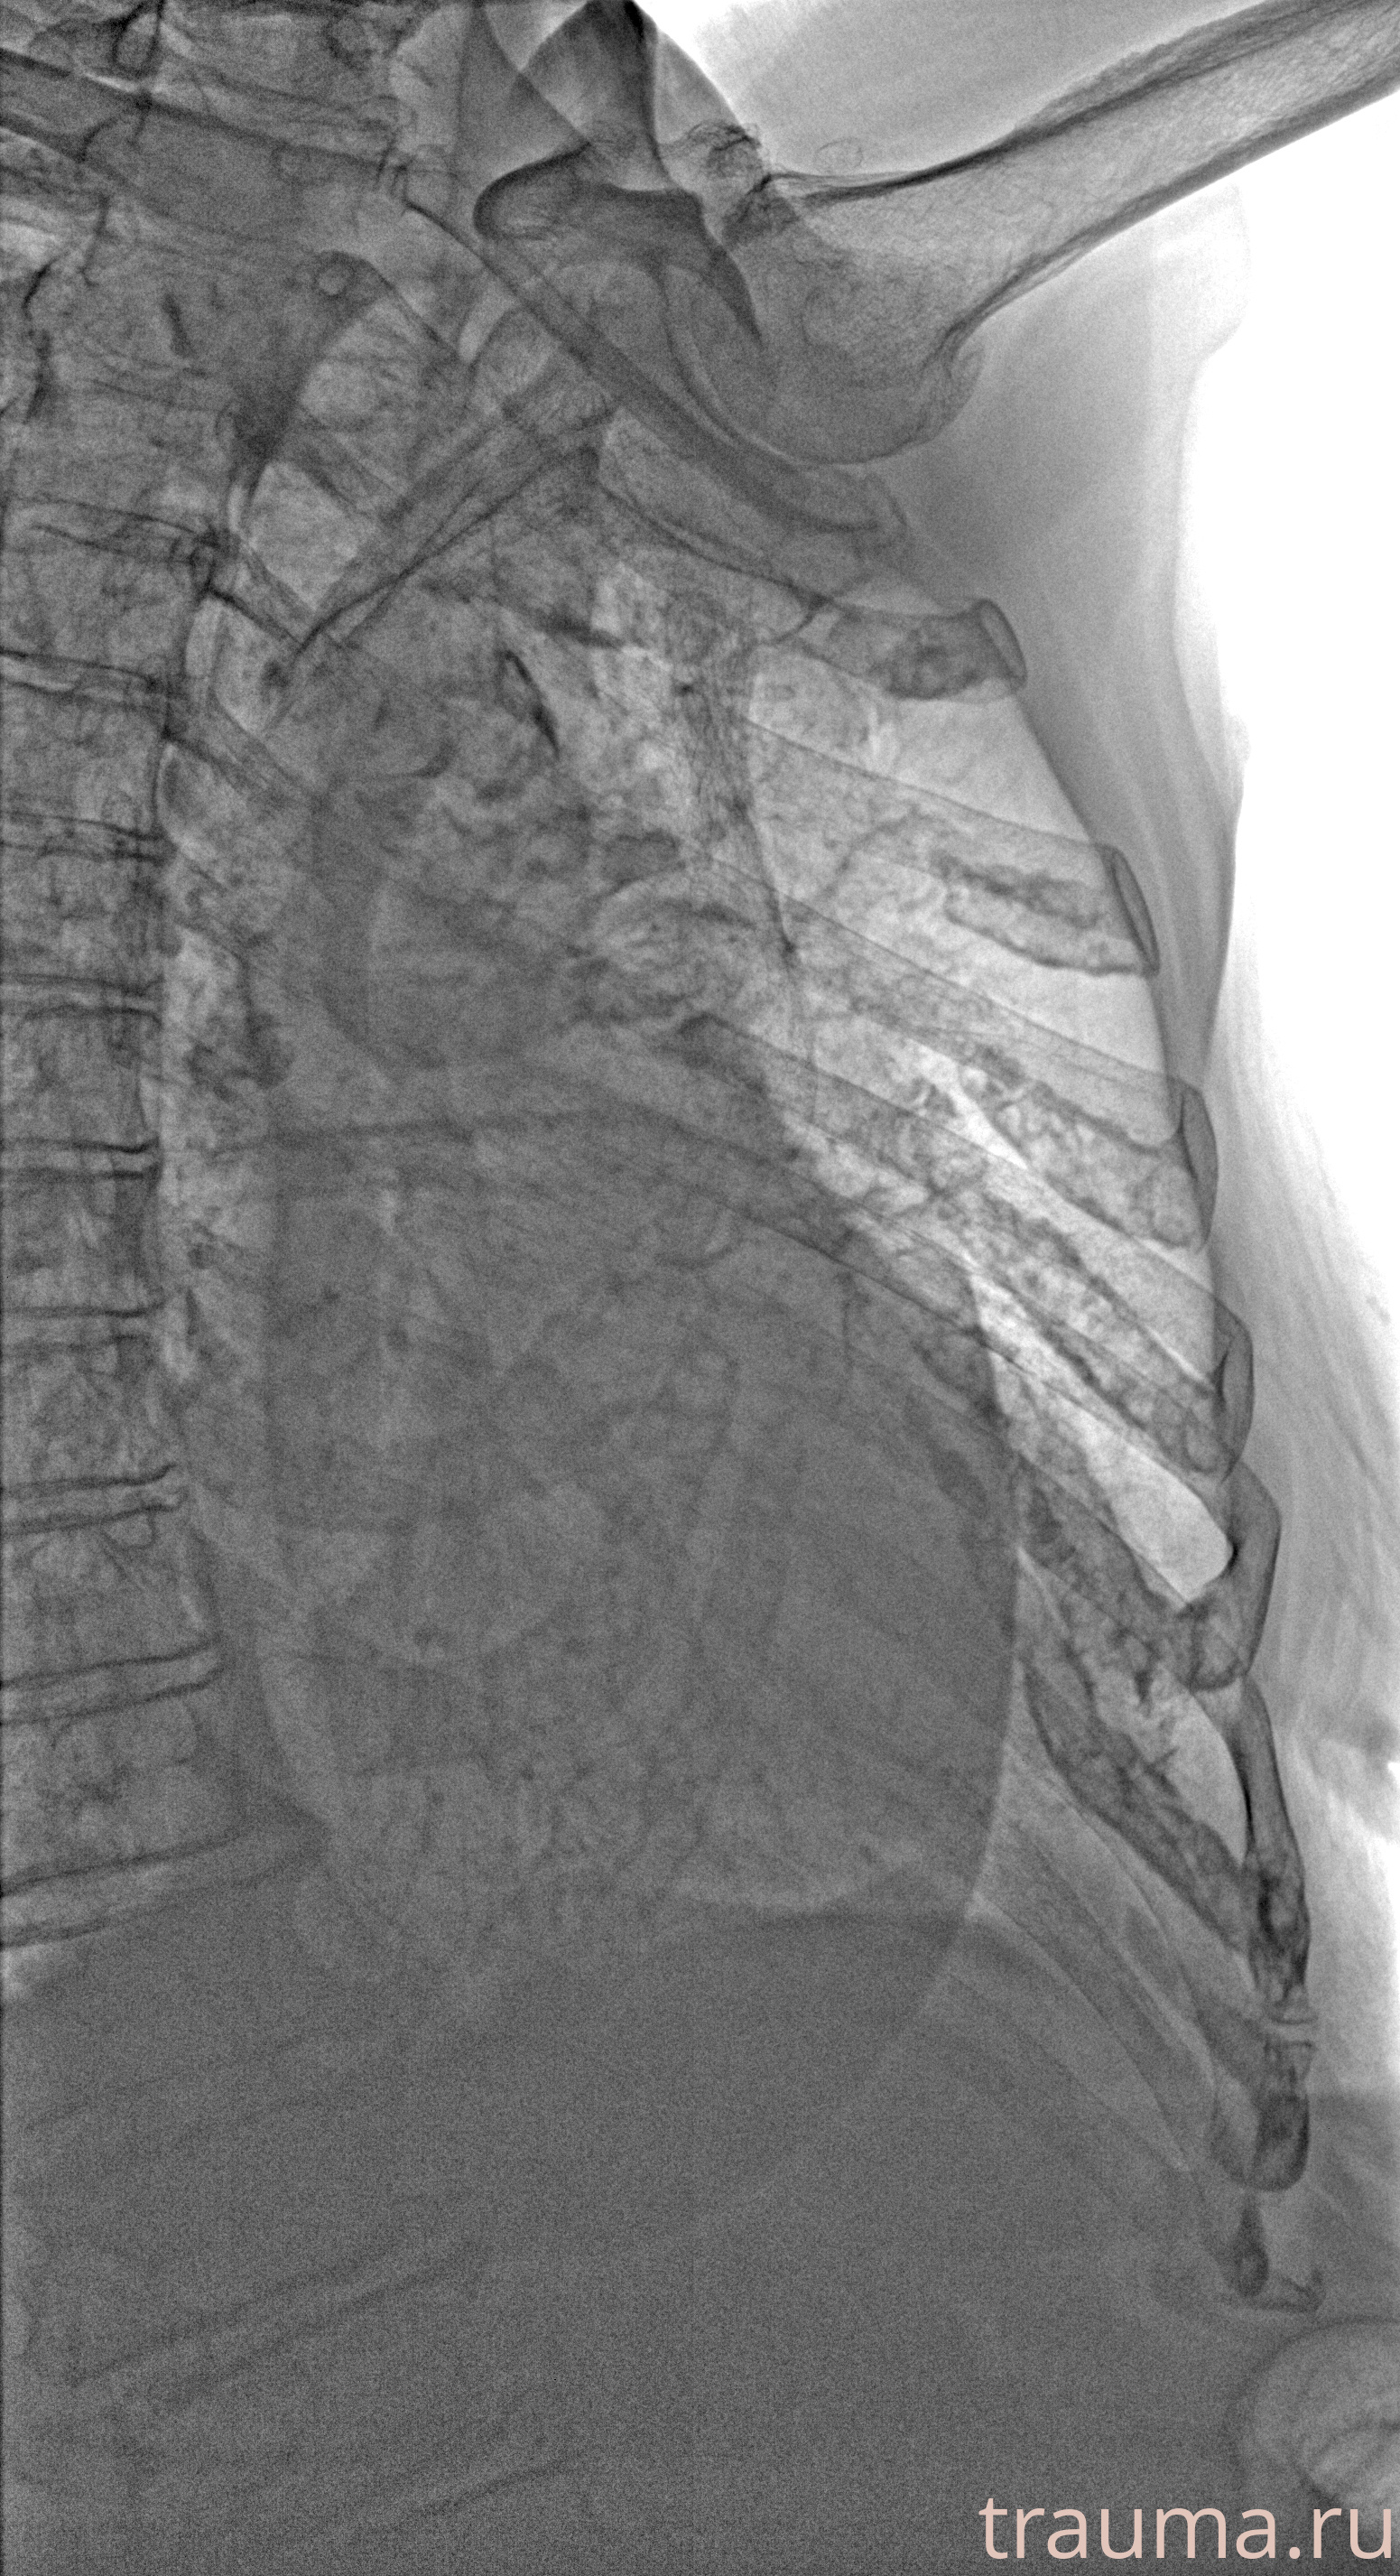

Рентген на дому: по вашему адресу приезжает врач-рентгенолог, травматолог-ортопед с мобильным рентгеновским аппаратом, проводит диагностику травмы или заболевания, делает необходимые рентгенограммы, дает рекомендации по дальнейшему лечению. Получить качественные снимки в домашних условиях возможно благодаря уникальной методике, разработанной МосРентген Центром для института  Склифосовского